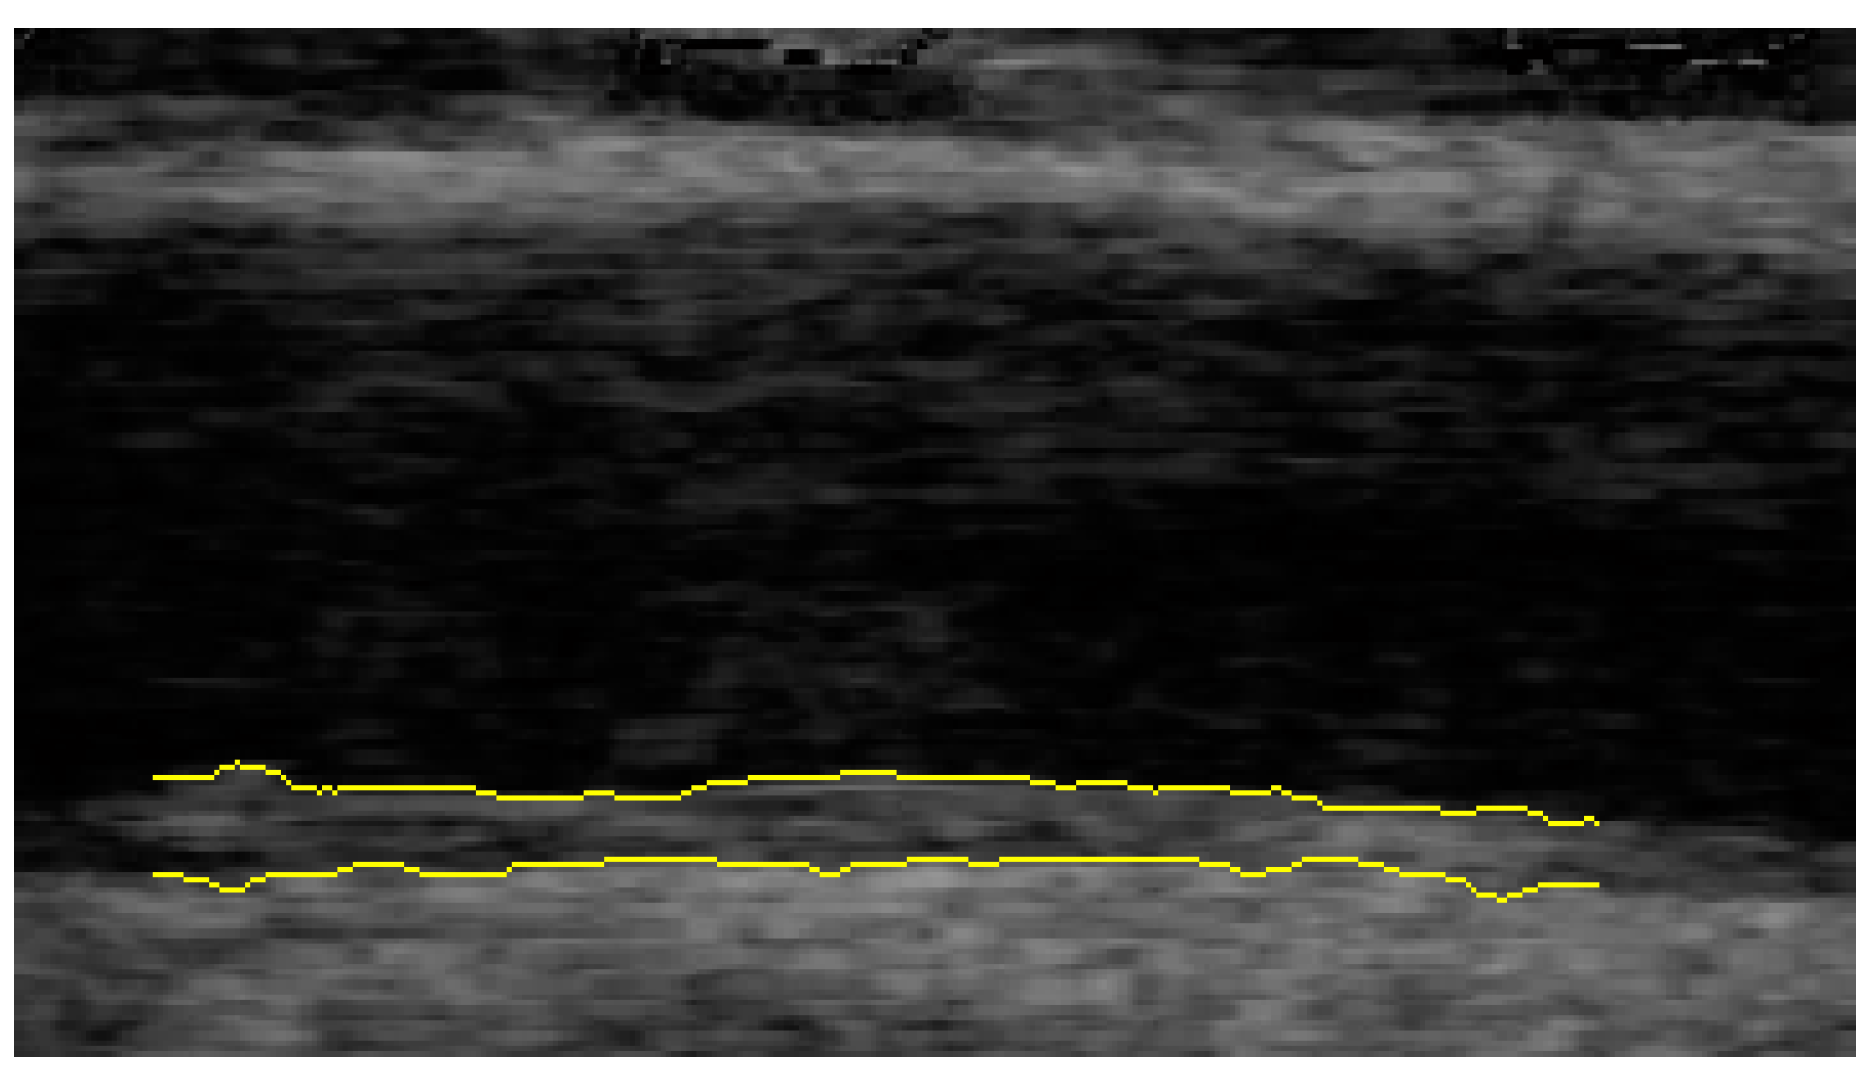

2.2. Ultrasound Examination

- Teynor, A.; Caviezel, S.; Dratva, J.; Kunzli, N.; Schmidt-Trucksass, A. An automated, interactive analysis system for ultrasound sequences of the common carotid artery. Ultrasound Med. Biol. 2012, 38, 1440–1450. [Google Scholar] [CrossRef] [PubMed]

- Schmidt-Trucksäss, A.; Cheng, D.C.; Sandrock, M.; Schulte-Mönting, J.; Rauramaa, R.; Huonker, M.; Burkhardt, H. Computerized analysing system using the active contour in ultrasound measurement of carotid artery intima–media thickness. Clin. Physiol. 2001, 21, 561–569. [Google Scholar] [CrossRef] [PubMed]

- Cheng, D.C.; Schmidt-Trucksäss, A.; Cheng, K.S.; Burkhardt, H. Using snakes to detect the intimal and adventitial layers of the common carotid artery wall in sonographic images. Comput. Methods Programs Biomed. 2002, 67, 27–37. [Google Scholar] [CrossRef]

- Dalla Pozza, R.; Pirzer, R.; Beyerlein, A.; Weberruss, H.; Oberhoffer, R.; Schmidt-Trucksass, A.; Netz, H.; Haas, N. Beyond intima–media-thickness: Analysis of the carotid intima–media-roughness in a paediatric population. Atherosclerosis 2016, 251, 164–169. [Google Scholar] [CrossRef]